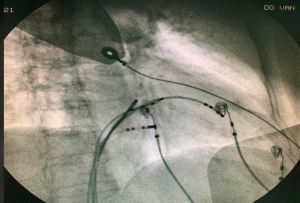

Phương pháp cắt đốt truyền thống được thực hiện dưới màn hình huỳnh quang tăng sáng sử dụng tia X để hướng dẫn đặt các catheter chẩn đoán trong buồng tim và định hình vị trí cắt đốt nhịp nhanh.

Hình nghiêng trái 45° và hình nghiêng phải 30° giúp định hình catheter trong cắt đốt nhịp nhanh kịch phát